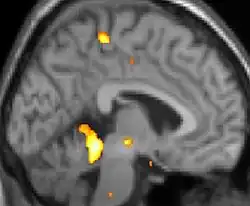

Positron emission tomography (PET) scans indicate the brain areas which are activated during attack only, compared to pain free periods. These pictures show brain areas that are active during pain in yellow/orange color (called "pain matrix"). The area in the center (in all three views) is activated only during cluster headaches. The bottom row voxel-based morphometry shows structural brain differences between individuals with and without CH; only a portion of the hypothalamus is different.[36]